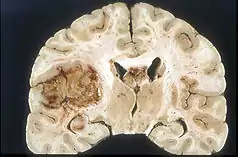

Malignant glioma is an extremely difficult to treat brain tumor that is a leading cause of death worldwide and half of cancer-related deaths.[14] Complications associated with treating glioma include the blood brain barrier (BBB).[14] This protective mechanism for the brain also raises challenges for drug delivery through the tight junctions between endothelial cells, only allowing small lipid-soluble drugs (<400 Da) to permeate.[14] Current delivery methods are surgery and chemotherapy. SDT has been implemented as a method to open the BBB and has shown success in opening tight junctions for delivery. Examples of sonosensitizers that have shown success in glioma treatment are hematopor-phyrin monomethyl ether (HMME), porfimer sodium (Photofrin), di-sulfo-di-phthalimidomethyl phthalolcyaninezinc (ZnPcS2P2), Photolon, 5-aminolevulinic acid (5-ALA), and rose bengal (RB).[14] These have shown to induce effects such as opening of the BBB, improved vascular permeability, and apoptosis of glioma cells.